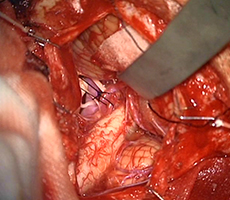

左前頭側頭開頭で動脈瘤クリッピング術を行った。手術中は脳血管撮影装置を用いたHybrid手術を施行し、動脈瘤の消失を手術中に確認する。

手術中MEP(運動神経)VEP(視力)モニタリングで術後の視力低下や手足の麻痺を予防します。

実際の手術所見

クリップ留置(瘤の消失:赤矢印)